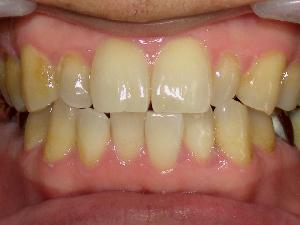

口腔内写真(口の写真)

口腔内の普段みることができかいところまでみることができます。

歯の位置、形、傾き、ブラッシングのくせ、歯肉の状態など写真で詳しく説明します。